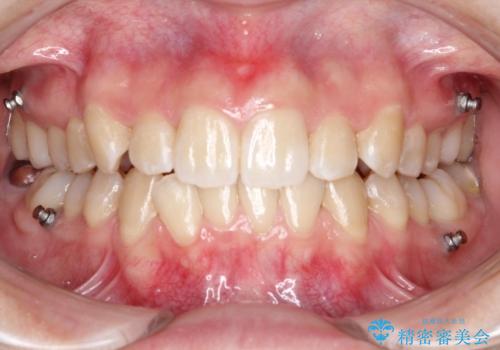

目立たない矯正で歯のデコボコと反対咬合を改善

- 前歯のデコボコ(叢生)と、前歯が上下逆の咬み合わせ(反対咬合)を主訴にご来院されました。精密検査の結果、歯列全体のスペースが不足していることが判明。患者様のご希望に合わせ、透明で目立ちにくい**インビザライン(マウスピース矯正)**による治療計画を立案しました。歯を抜かずに、歯列全体を奥(遠心)へ移動させることで、歯が並ぶスペースを確保し、叢生と反対咬合を同時に改善することを目指します。

今回の矯正治療では、透明なマウスピース型の装置インビザラインを使用しました。この装置は目立たず、取り外しが可能なため、食事や歯磨きも普段通り行えます。治療は、緻密な治療計画に基づき、段階的に作製されたマウスピースを交換していくことで、遠心移動という方法で奥歯から徐々に歯列全体を後方へ動かしました。これにより、不足していたスペースを確保し、前歯のデコボコを解消。同時に、上下の歯の前後的な関係を改善することで、反対咬合も正常な咬み合わせへと導きました。見た目も機能も改善し、自然で美しい笑顔を獲得していただけました。